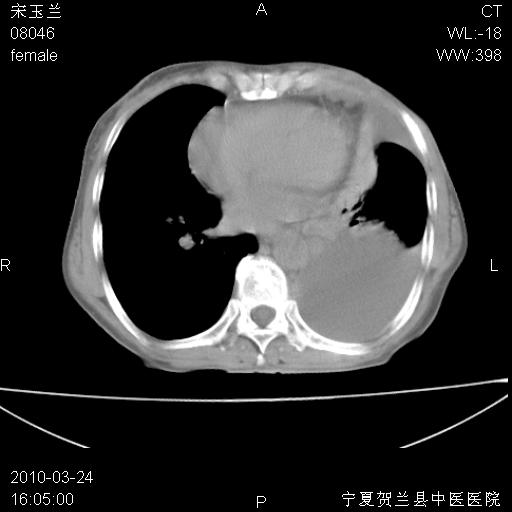

以下是引用zxl51642在2010-3-24 18:49:00的发言:[br]结合乳腺癌术后病史,考虑双肺及纵隔淋巴结多发转移、左侧胸膜转移并左侧大量胸水、左下肺膨胀不全。